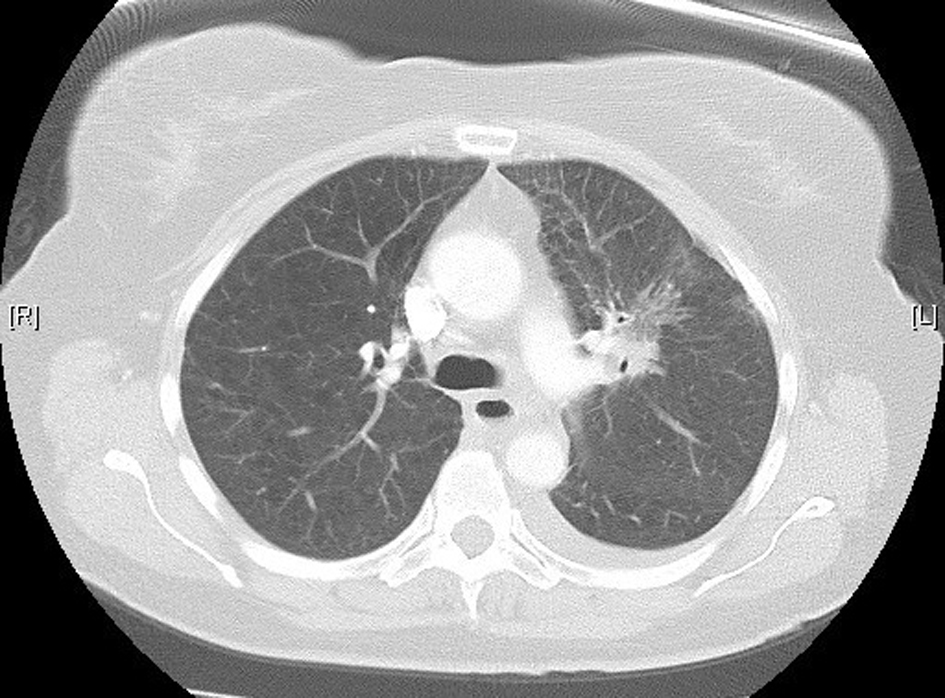

A 61-year-old female was diagnosed with stage IV (T2a, N2, M1b) NSCLC in June 2012. Positron emission tomography (PET) scan showed evidence of oligometastatic disease involving the right adrenal gland. She subsequently had a laparoscopic resection of the right adrenal gland in June 2012; pathology results were consistent with a metastatic, poorly differentiated adenocarcinoma of lung origin. She began concurrent chemoradiotherapy in July 2012, with cisplatin and etoposide, and radiotherapy (60 Gy). Treatment was complete by August 2102. Restaging computed tomography (CT) scan showed regression of the primary tumor. There was no evidence of any interstitial lung disease (Fig. 1). In October 2012, 56 days following completion of radiotherapy, maintenance pemetrexed was commenced, 500 mg/m2 every 21 days, with supplemental vitamin B12 and folic acid.

![]() Click for large image | Figure 1. High-resolution lung computed tomography before pemetrexed administration. |